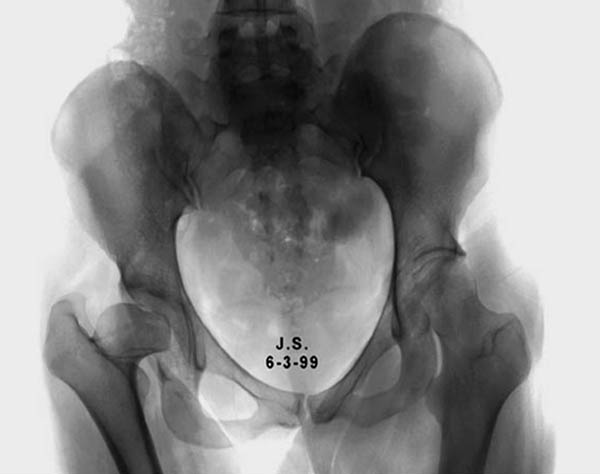

Представленный случай имеет схожесть...., и последний снимок после 2 х лет.

Здесь комбинированная патология тазобедреннего сустава, связанная с высокостоящим вертелом и отсутствием (ротирована?) шейкой. А на стороне вертлужной впадины диспластический сустав. Обычно высоко расположенный вертел приводит к уменьшению силы мышц абдукторов, но отстутствие шейки привело к вертикальному расположению сил в суставе. Боли появляются из-за вертикального давления, а неровные контуры головки приводят к ограничению движений в суставе. Такое состояние быстро изнашивает сустав, и больные в молодом возрасте заканчивают тотальным протезированием.

Для оценки пригодности сустава надо сделать снимки во внутренной и наружной ротации, а также с отведением и приведением каждого сустава. Сравнительные снимки покажут возможный подвывих и укорочение, а также состояние суставной щели. 3D Компьютерная Томография покажет возможную ротацию шейки.